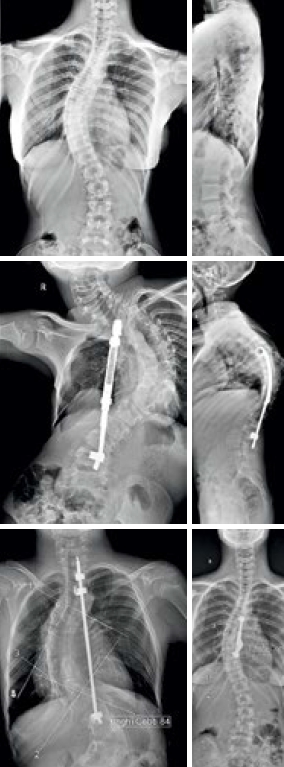

Diagnosticul se face prin examen radiografic. În cazurile în care etiologia nu poate fi apreciată radiologic se folosesc examinări IRM sau CT. Examenul radiologic are rolul de a confirma diag-nosticul, de a identifica atunci când este posibil etiologia şi de a aprecia evoluţia curburii. Curbura este măsurată prin metoda Cobb şi este apreciată în grade. La modul general, o scolioză este considerată semnificativă, dacă este mai mare de 25-30 de grade. Scoliozele de peste 45-50 grade sunt considerate severe şi necesită tratament mai agesiv.

Tratamentul scoliozei se face prin gimnastică medicală respiratorie, corset, stimulare electrică, tratament chirurgical. Aprecierea unghiului de curbură este foarte important în adoptarea atitudinii terapeutice. Scoliozele cu grad de curbură mai mic de 20 grade trebuie tratate conservativ, iar pacienţii trebuie examinaţi la 3-6 luni pentru a aprecia progresia. Formele cu unghi între 20 grade şi 40 grade beneficiază de gimnastică medicală şi corset. Cele peste 40-50 grade necesită corecţie chirurgicală.

Tehnologia radiologică actuală permite un diagnostic corect al scoliozei, în urma cărora se poate stabili protocolul terapeutic şi totodată permite o evaluare în dinamica succesului terapeutic cu doze minime de iradiere.